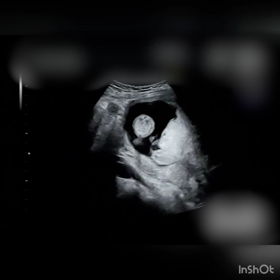

【4人目22wの健診】なかなか確定しない性別。笑